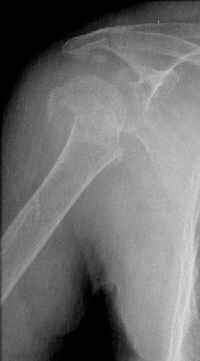

Hello,I am presenting a case of 80 year old male patient right handed known case of hypertension, diabetes and history of CVA 2 years back had a fall in the hosue 10 days back and came to me for pain and ecchymosis around the right shoulder. Xray shows evidence of comminuted fracture proximal humerus extraarticular. He is a doctors father and the doctor wants to know is there any minimally invasive procedure we can do ... I have advised him to go for complete surgery in the form of the AO locking plate under general anesthesia. He is a little reluctant for complete general anaesthesia. My questions to the house is ...1. Is there any other option besides the locking plate ?? (Less invasive) 2. If he is not medically fit for surgery, then can we leave him alone if yes what are the chances of going it into non union? Awaiting your reply Dr Neeraj Bijlani

Another option could be closed nailing, see an example, the surgery was done 2 days ago. In common such surgeries are performed under regional anesthesia, not general.

Fragments now look severely displaced.

The fracture is completely displaced in the axial view. It is probably possible to align it with the patient in the vertical position, i.e. sitting or standing. However, I would use a locking plate for the tremendous pain relief it offers.